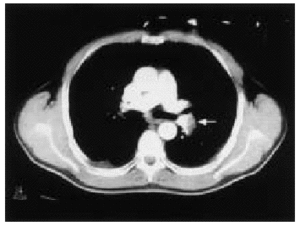

Debido a un nuevo episodio similar a los previos, acudió al servicio de urgencias de nuestro hospital. La exploración sistémica fue normal; en la radiografía de tórax se observaban 2 pequeños infiltrados en ambos lóbulos superiores, y en la gasometría la PaO2 fue de 56 mmHg; la PaCO2 de 27 mmHg y el pH de 7,49. En el electrocardiograma (ECG) se apreciaba una onda T negativa de V1 a V4. El hemograma, la bioquímica y el estudio de coagulación fueron normales. Se realizó una gammagrafía de ventilación-perfusión en la que se objetivó un déficit completo de perfusión del pulmón izquierdo (fig. 1). La tomografía computarizada (TC) helicoidal reveló una imagen compatible con un trombo en la arteria pulmonar izquierda y dos infiltrados triangulares de base periférica en LSD y LMD (fig. 2). En el ECO-Doppler de las extremidades inferiores no se objetivaron trombos en ninguna zona, con dilatación de las cavidades derechas y presión sistólica en la arteria pulmonar de 39 mmHg.

Figura. 1. Gammagrafía de perfusión. Se aprecia la ausencia de perfusión del pulmón izquierdo.

Permaneció estable hemodinámicamente (presión arterial de 110/60 mmHg; frecuencia cardíaca de 70-80 lat/min en RS) y con una SatO2 en torno al 95-97% con oxígeno por mascarilla al 40%. Con el diagnóstico de TEP masiva se realizó fibrinolisis con r-TPA (100 mg en 2 h). No hubo complicaciones y la rápida mejoría clínica (desapareció la disnea, frecuencia cardíaca de 40 lat/min; SatO2 del 100% con oxígeno a 2 l/min por gafas nasales) se comprobó con la realización de nueva gammagrafía y TC, en los que se constató la disolución del trombo y la reperfusión del pulmón izquierdo. Se continuó tratamiento con heparina sódica y posteriormente dicumarínicos orales (tasa de protrombina 30%; INR = 2,1). Tras 2 semanas de tratamiento fue dado de alta a su domicilio. Durante el ingreso se realizaron los siguientes estudios: estudio de hipercoagulabilidad, que fue normal; se descartó neoplasia subyacente (TC de tórax, abdomen y pelvis; ecografía abdomen y pelvis; gammagrafía ósea; marcadores tumorales); se descartó foco embolígeno (ECO-Doppler de miembros inferiores, flebogammagrafía; iliocavografía) y se descartó enfermedad reumatológica.